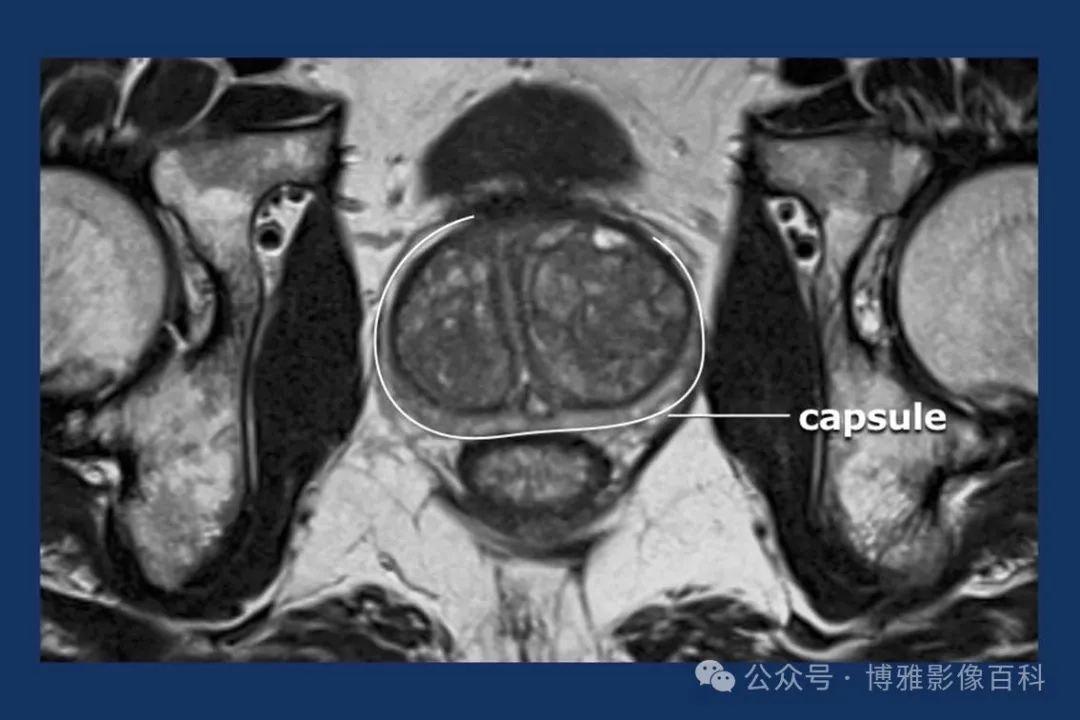

前列腺良性增生患者的轴向T2 图像,其他方面正常。外周带是一薄层均匀的高信号,边界清晰连续性的低信号包膜。移行带通常表现为不均匀中等信号,病灶被边界清楚的BPH良性前列腺增生结节所取代。精囊具有均匀T2高信号。未见淋巴结肿大。